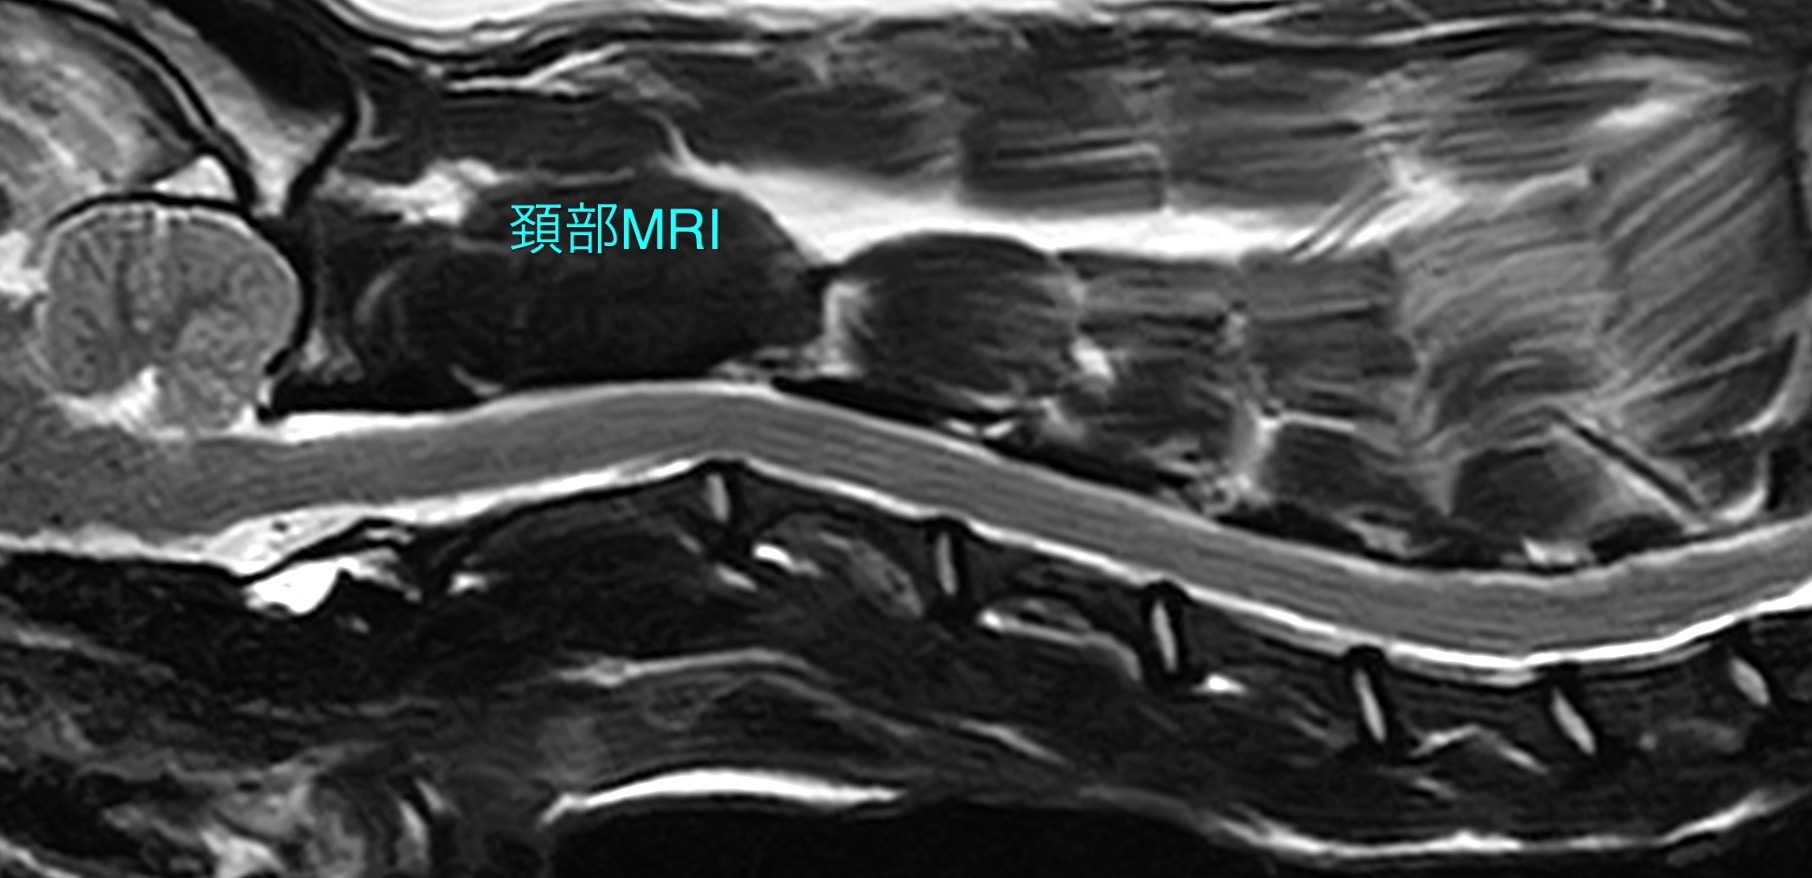

動画の子(11歳のジャックラッセルテリア)は、約2年前からこの病気が発症し、緩やかに症状が進行してきていたため当院に診断精査を希望され来院されました。MRI検査で脳・頚髄と頚部筋肉に明らかな異常所見は認められず、脳脊髄液検査にも異常は認められませんでした。以前から副腎皮質機能亢進症を患っていたことから、「副腎皮質機能亢進症を原因とした偽性ミオトニア」を疑い、筋電図検査を行ったところ、静止状態にも関わらず規則的な放電を示す"複合反復放電"が複数の筋肉で検出されたため、確定診断としました。

頚部MRI